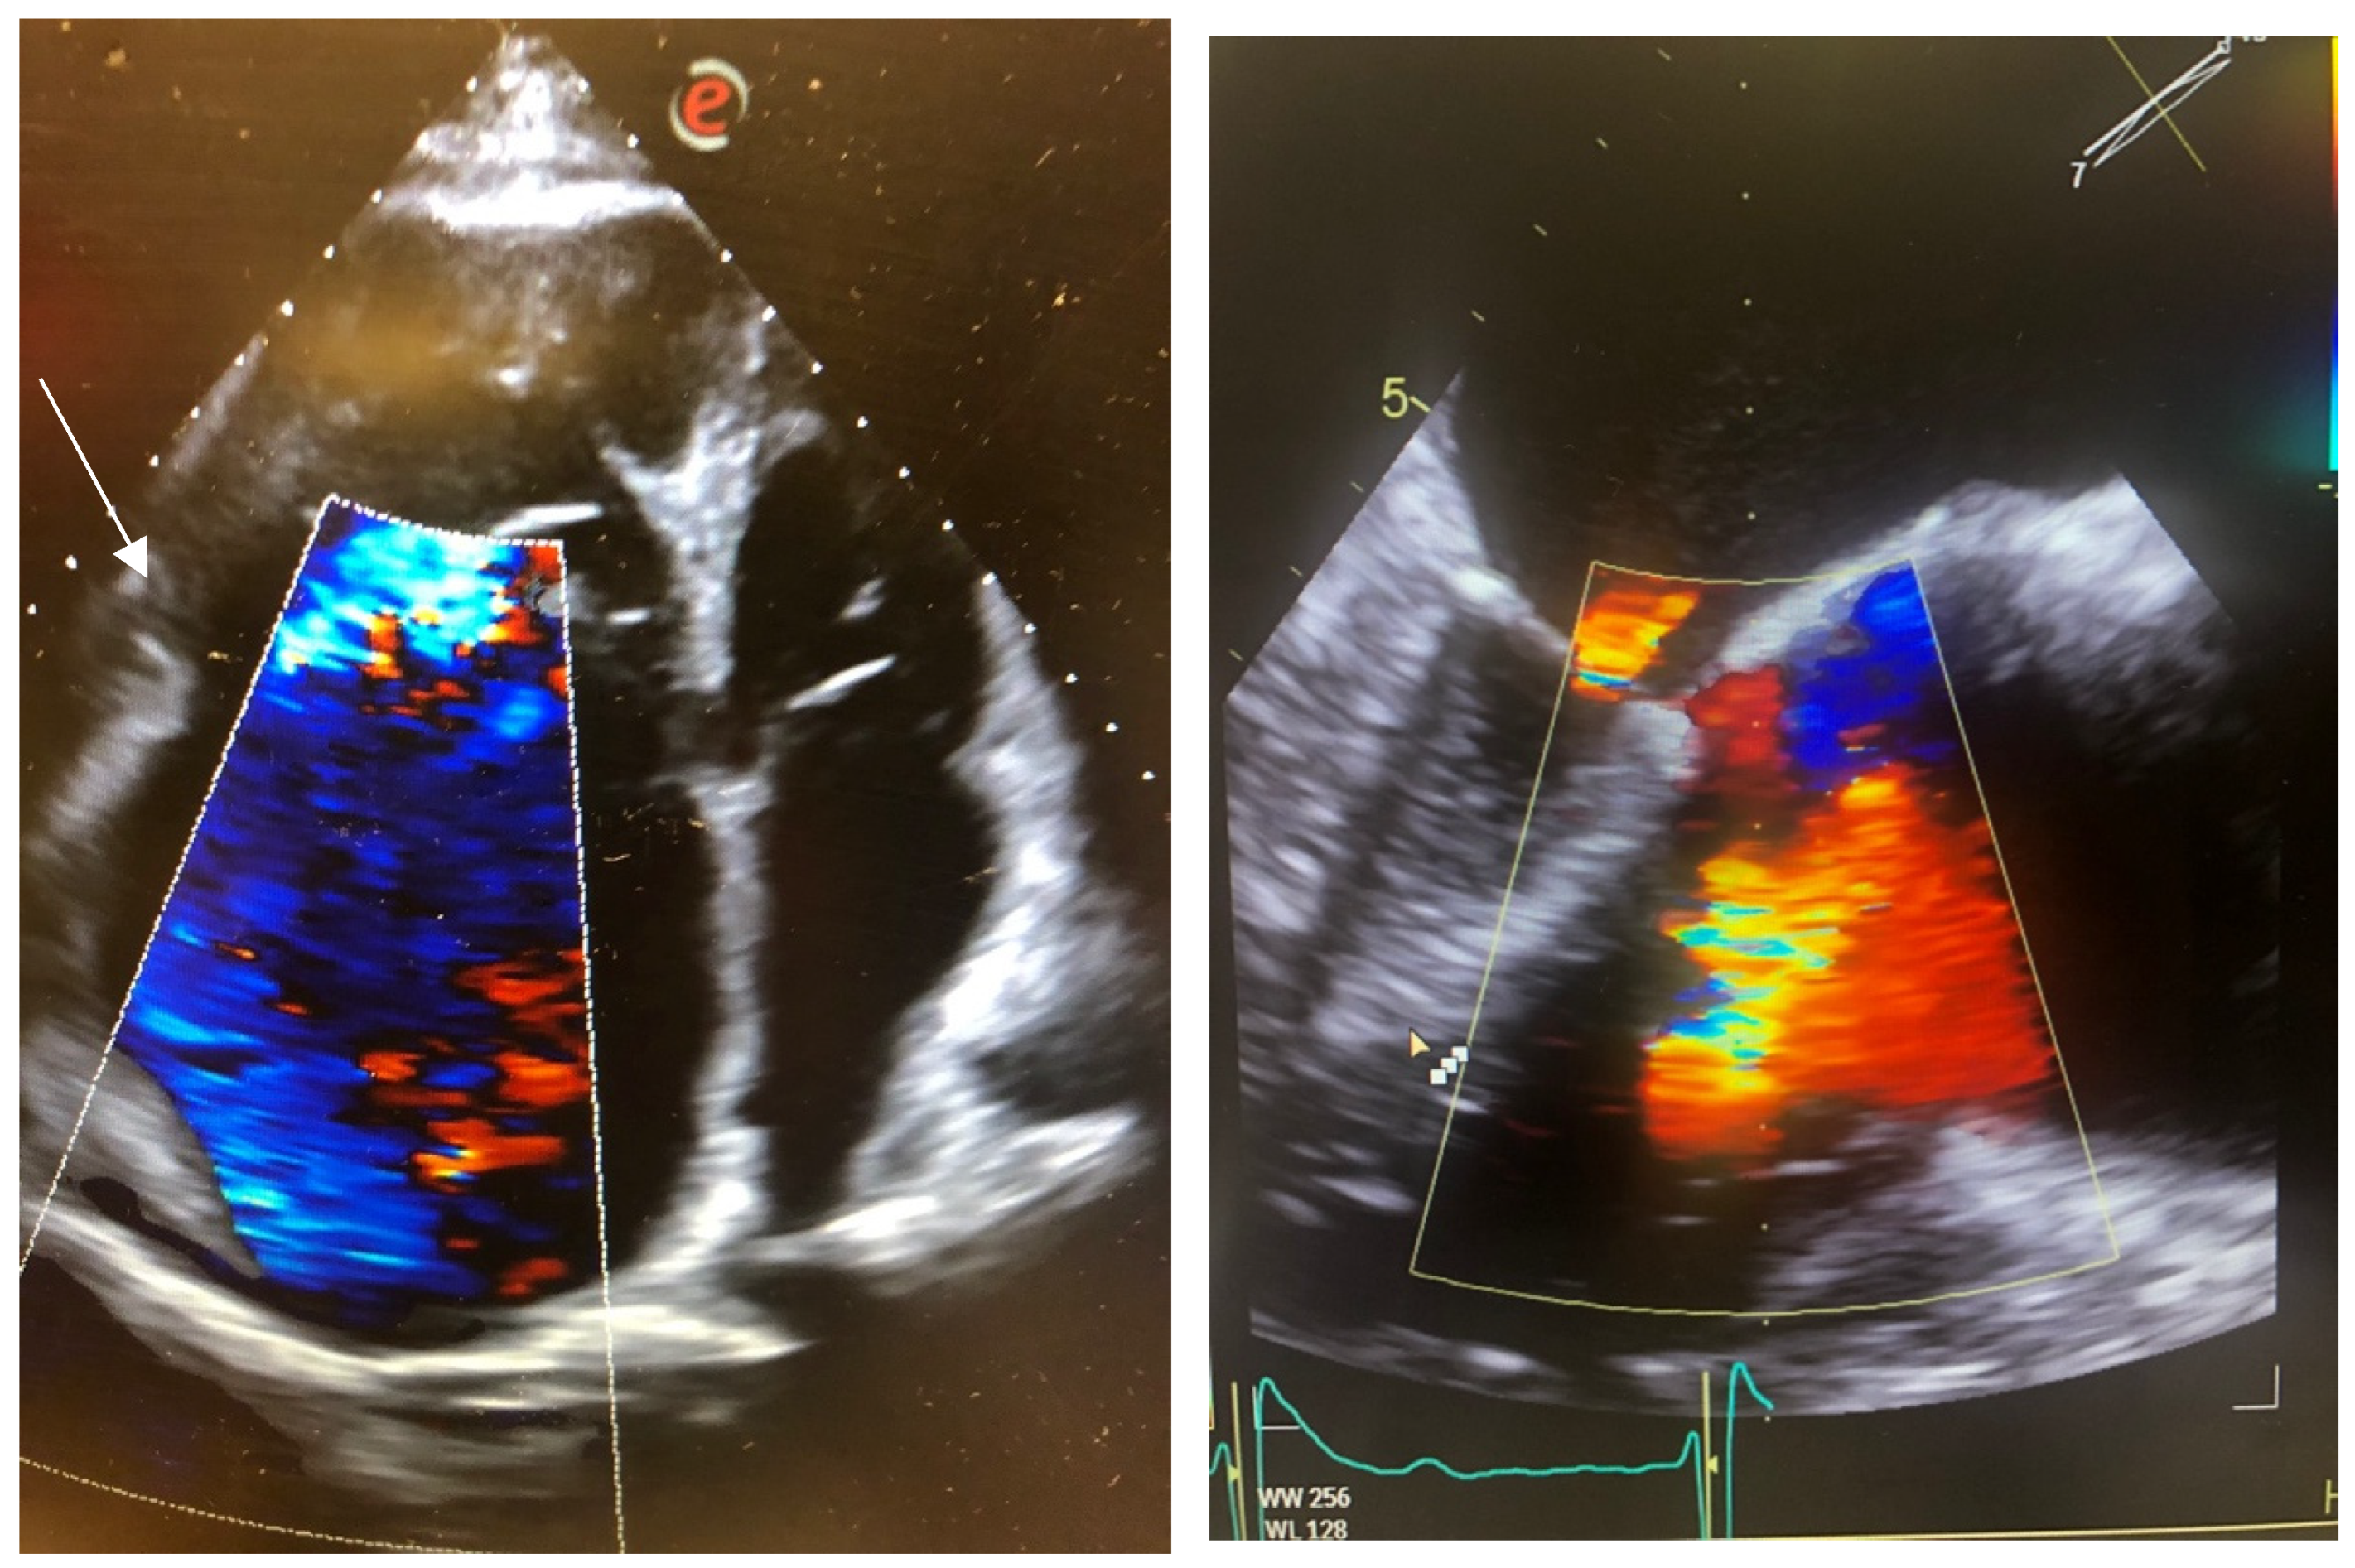

2.1. Case 1

2.2. Case 2

2.3. Case 3